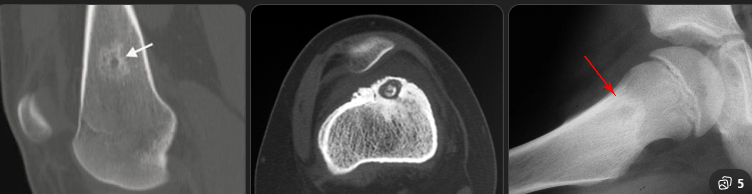

Homem jovem

Dor noturna que melhora com AAS

Nidus radioluscente + esclerose periférica

Diagnóstico por imagem (TC)

Tratamento: ablação por radiofrequência

Osteoma osteoide